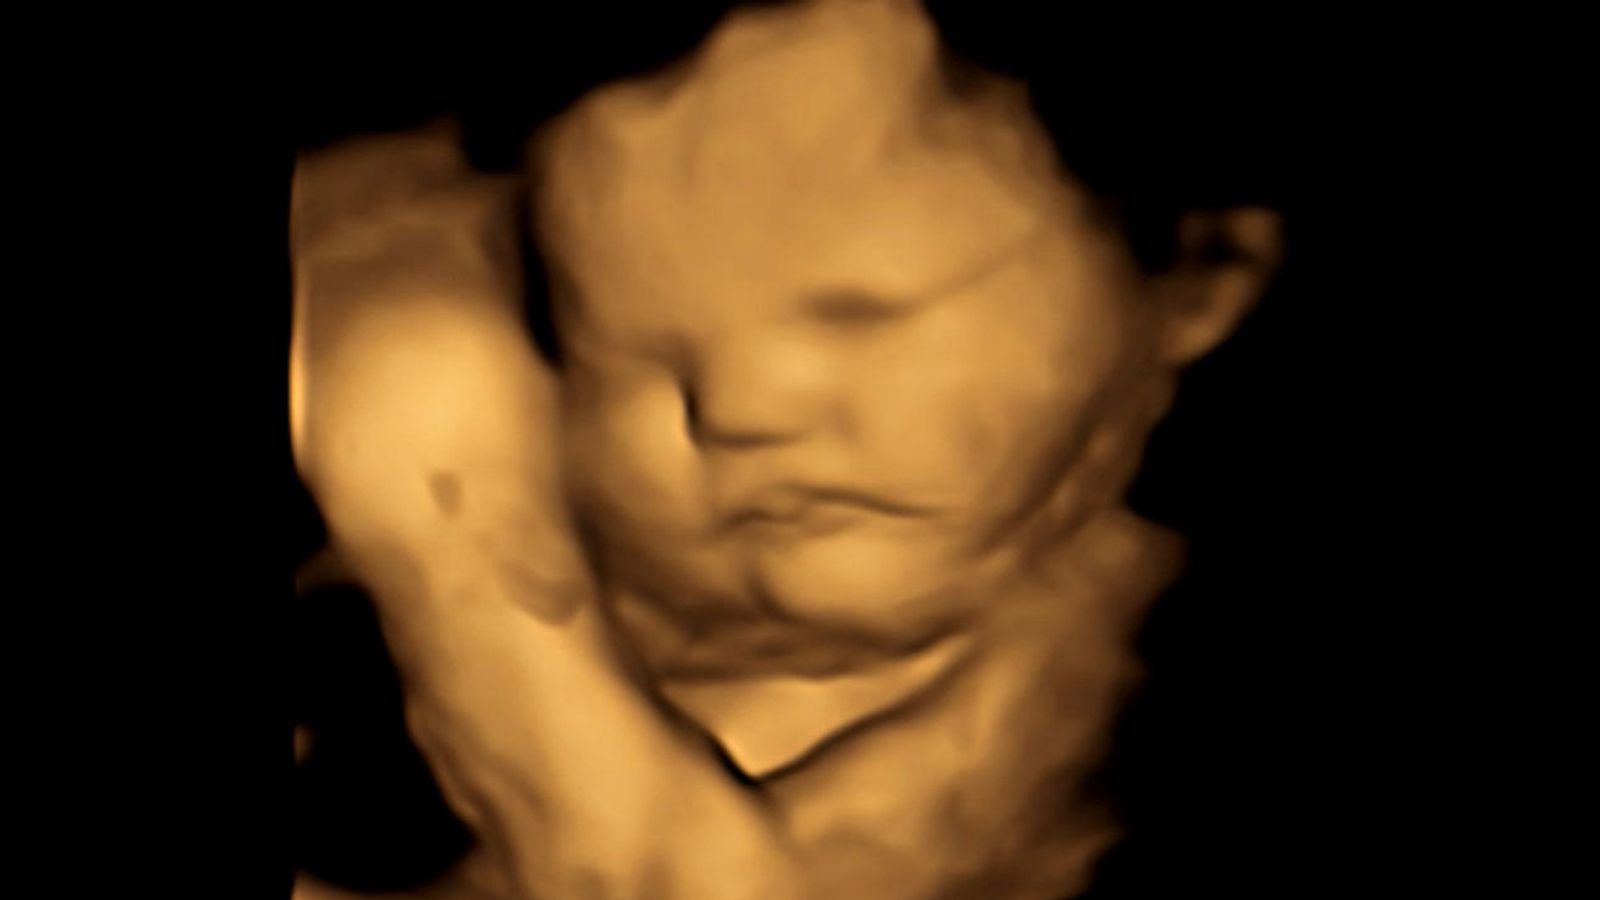

Not Feeling Connected To Baby In Womb . Learn what typical fetal movements feel like, what causes reduced movements, and when to call a health. Learn how oxytocin, experience and support can influence bonding, and. Find out how prenatal bonding can benefit your. learn how to connect with your unborn child through touch, sound, and visualization. Find out how to enhance the. Your baby can hear and feel movement before they are born. How does stress affect their development and bonding? learn how bonding happens between parents and babies, why it may not be immediate, and what factors can interfere with it. bonding is the parental feeling of being connected with the infant, experiencing a sense of unconditional love and closeness. bonding with your baby when they are in the womb can help their development after they are born. can babies feel unwanted or rejected in the womb?